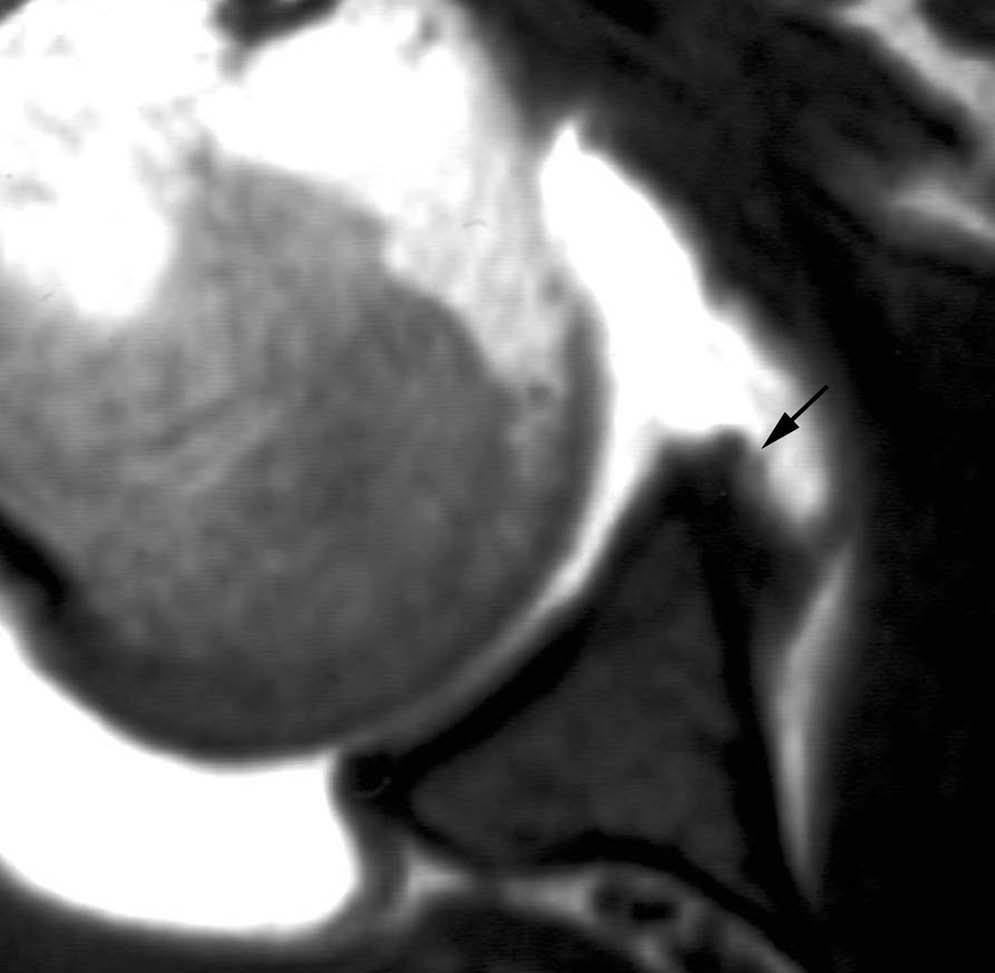

POLPSA (posterior labral periosteal sleeve avulsion)

Esta lesión se asemeja a la ALPSA, pero ocurre en el borde glenoideo posterior. El LG se halla desplazado hacia dentro y por detrás del borde glenoideo posterior. El mecanismo de producción del POLPSA es una dislocación posterior, y por tanto se puede encontrar también un Hill Sachs invertido19 (fig. 14).

. Artrorresonancia axial T1 con supresión grasa donde se observa una rotura del labio glenoideo posterior con desplazamiento posteromedial (flecha). Nótese la situación del labio glenoideo en comparación con una rotura sencilla, no desplazada, que se observa en la figura 13. Obsérvese la presencia de una lesión de Hill-Sachs invertida (cabezas de flecha), en relación con una dislocación posterior con reducción.Lesión de Bennett